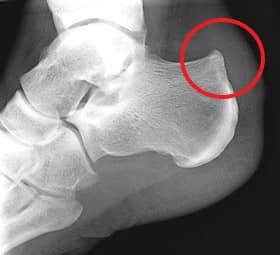

• Haglund's deformity. This is a condition in which there is enlargement of the bone on the back of the heel. This enlarged bone can rub on the Achilles tendon and cause inflammation and pain.

Bone spur

Haglund's deformity is when there is abnormal bone growth near where the Achilles tendon attaches to the heel bone.